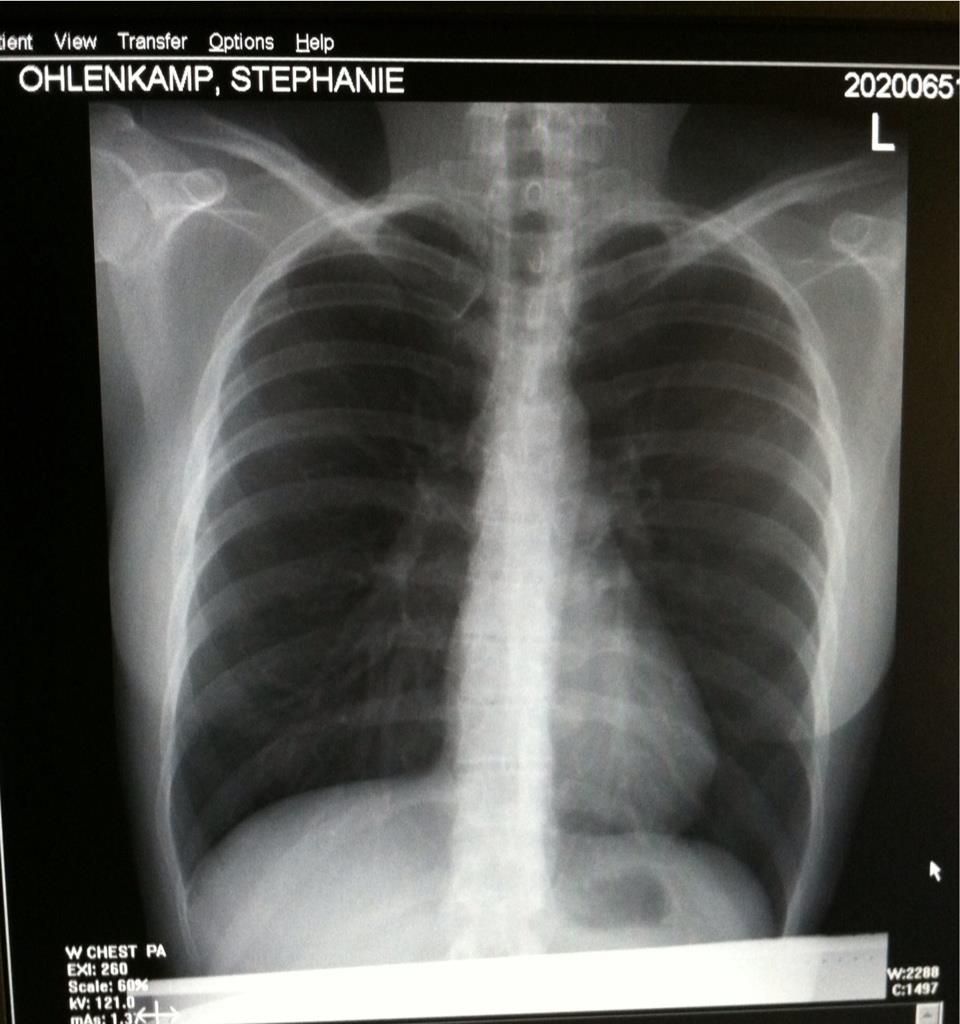

Costochondritis Show On X Ray . Doctors can usually diagnose a child, adolescent, or young adult by asking questions about their medical. Key sign is pain on. Costochondritis is inflammation in your costochondral joints — the cartilage that joins your ribs to your sternum (breastbone). A chest computed tomography angiogram (cta) may be obtained if a dissection is suspected based on history, exam findings, or the presence. There is no laboratory or imaging test to confirm a diagnosis of costochondritis. It can be scary to feel chest pain, especially if it’s on the same. But a health care provider might order certain tests,.